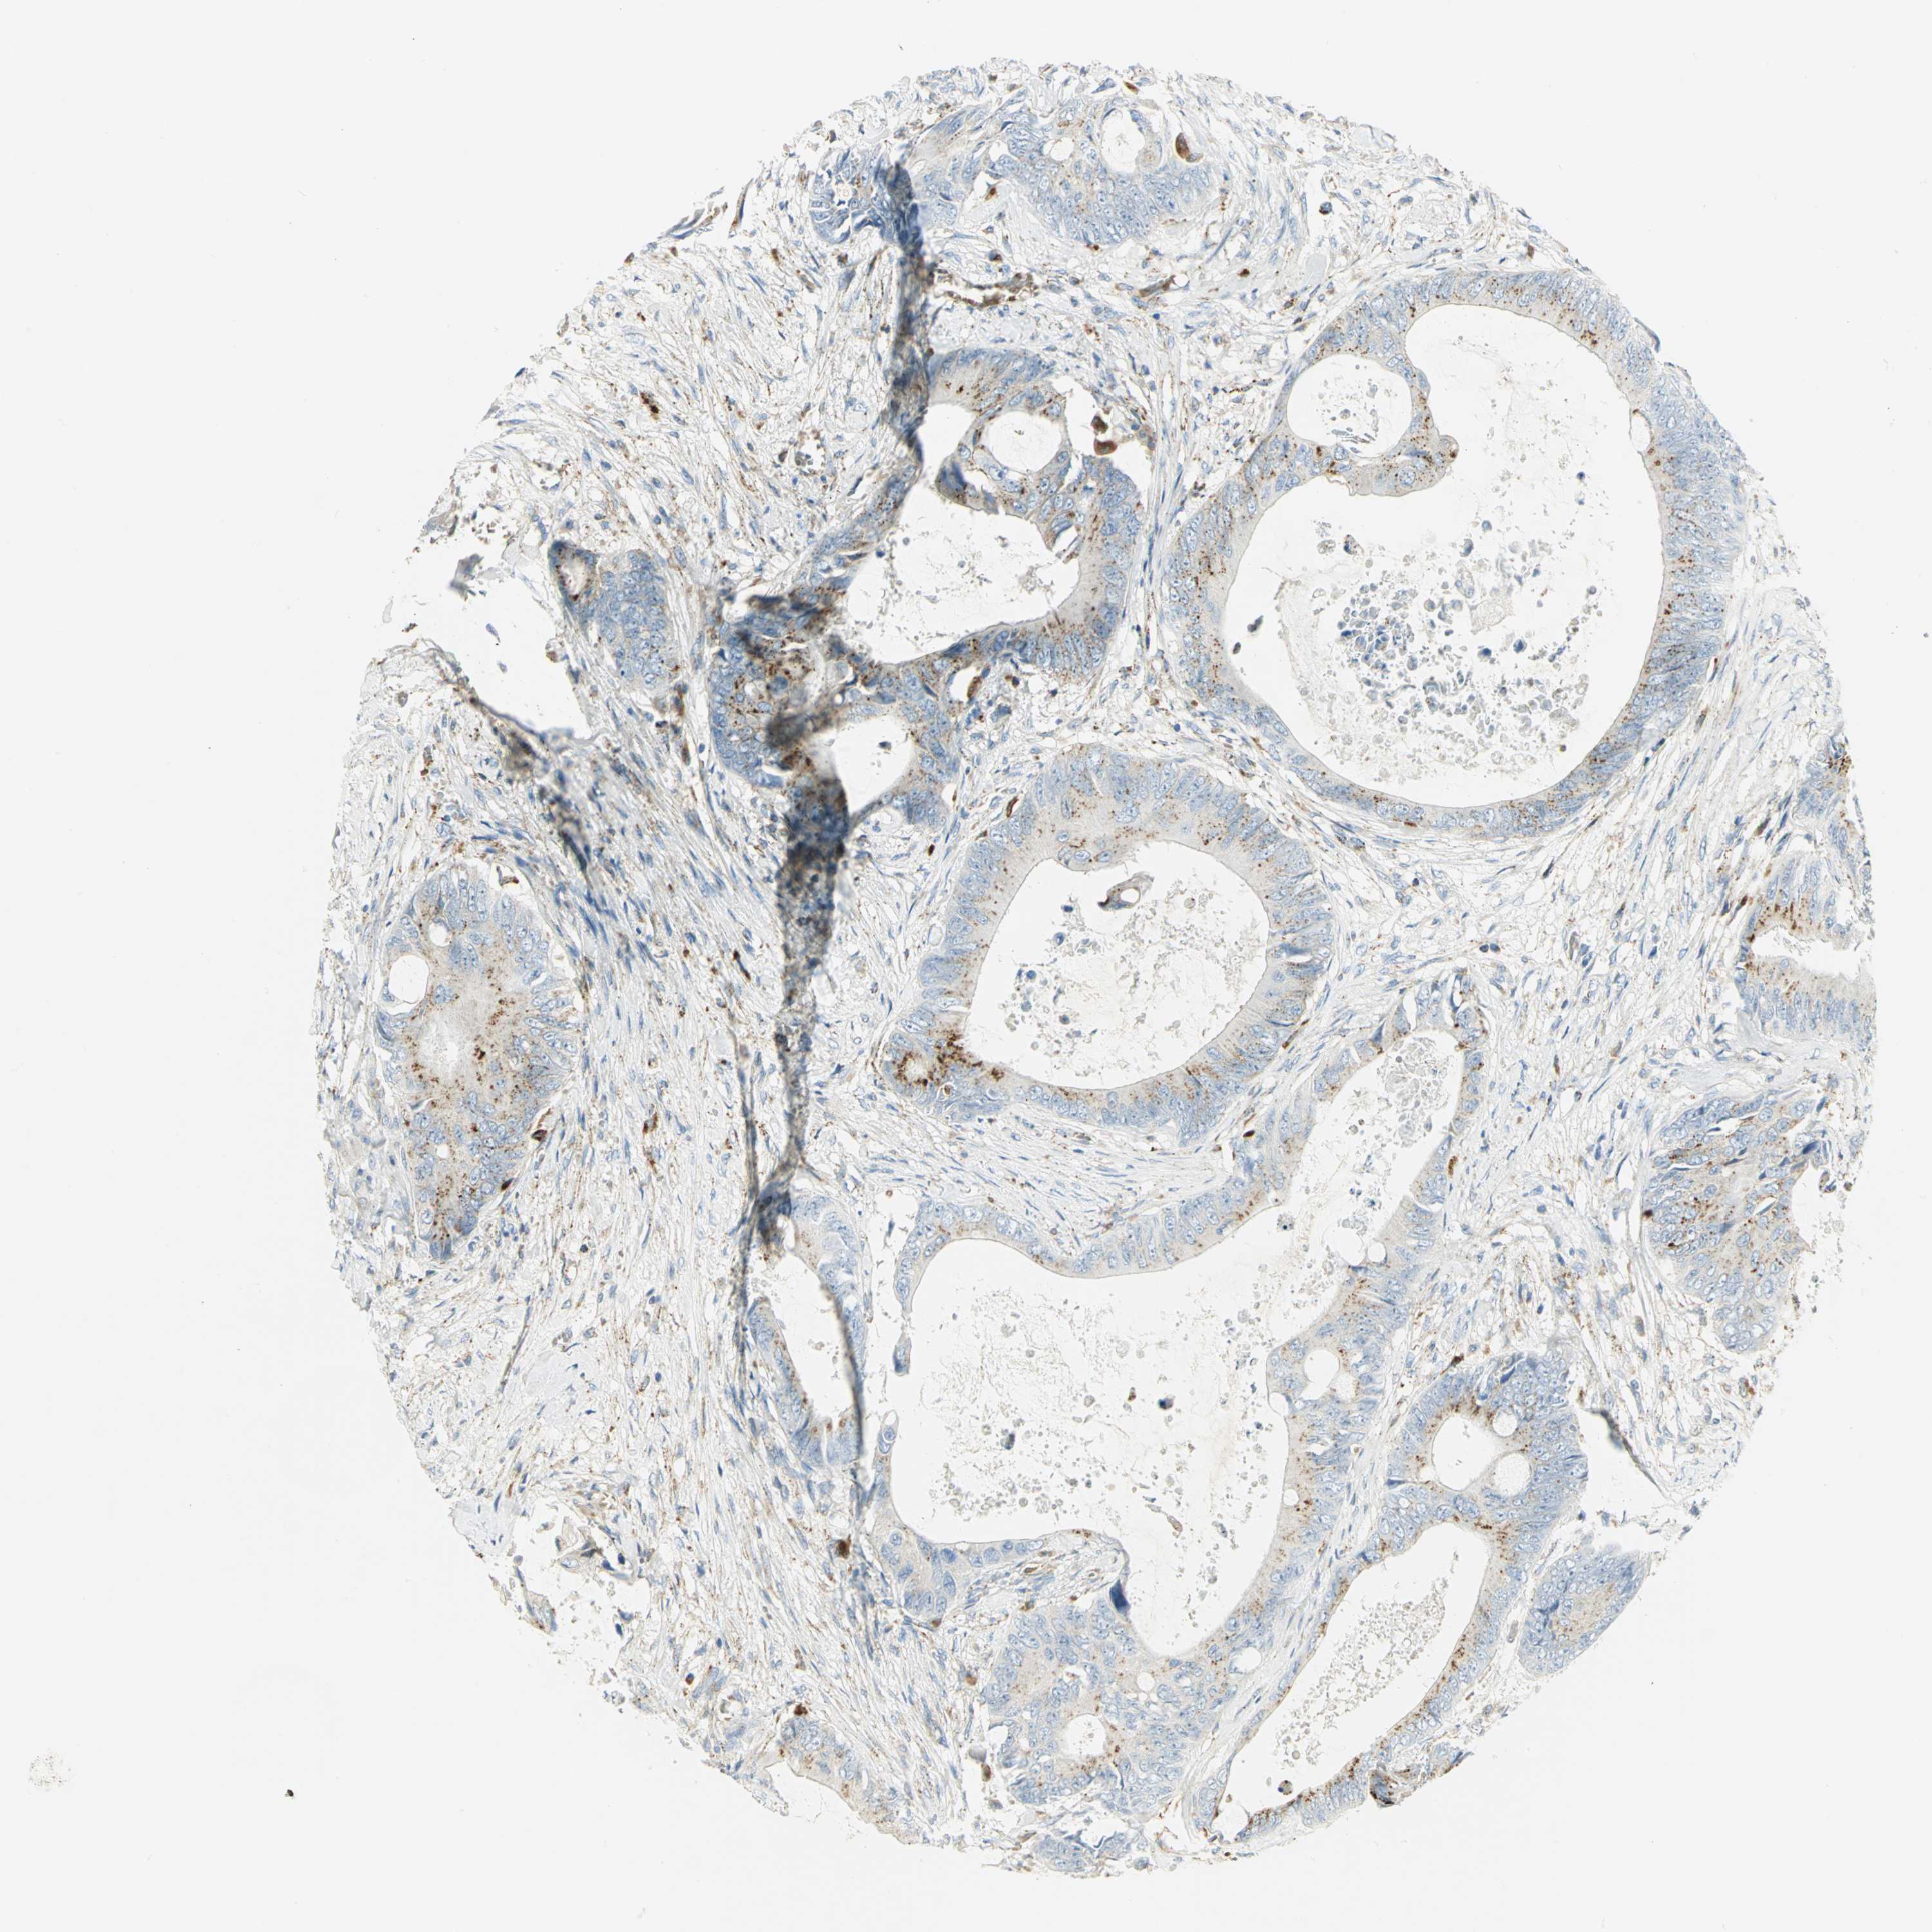

CANCER COLORECTAL CANCER Show tissue menu

COAD TCGA COAD VALIDATION READ TCGA READ VALIDATION PROTEIN COAD CPTAC PROTEIN EXPRESSION

ANTIBODIES

AND

VALIDATION